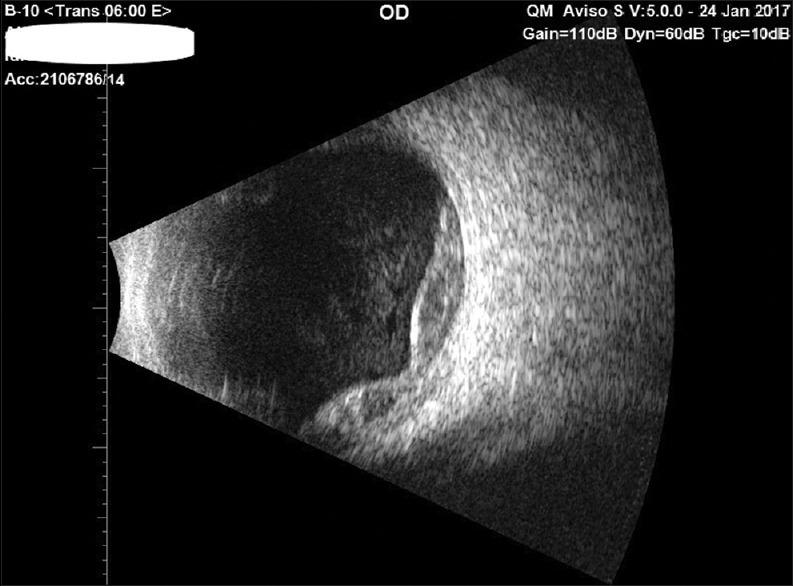

The purpose of the study is to report a case of peripheral exudative hemorrhagic chorioretinopathy (PEHCR), managed surgically with favorable visual outcome. A 66-year-old female presented with painless visual loss due to dense vitreous and subretinal hemorrhage extending from the far periphery to the macula. Pars plana vitrectomy (PPV) with subretinal tissue plasminogen activator (TPA) injection was performed resulting in good anatomical and visual outcome. PEHCR can present with severe visual loss. Surgical management with PPV and subretinal TPA injection might result in favorable anatomical and visual outcome.